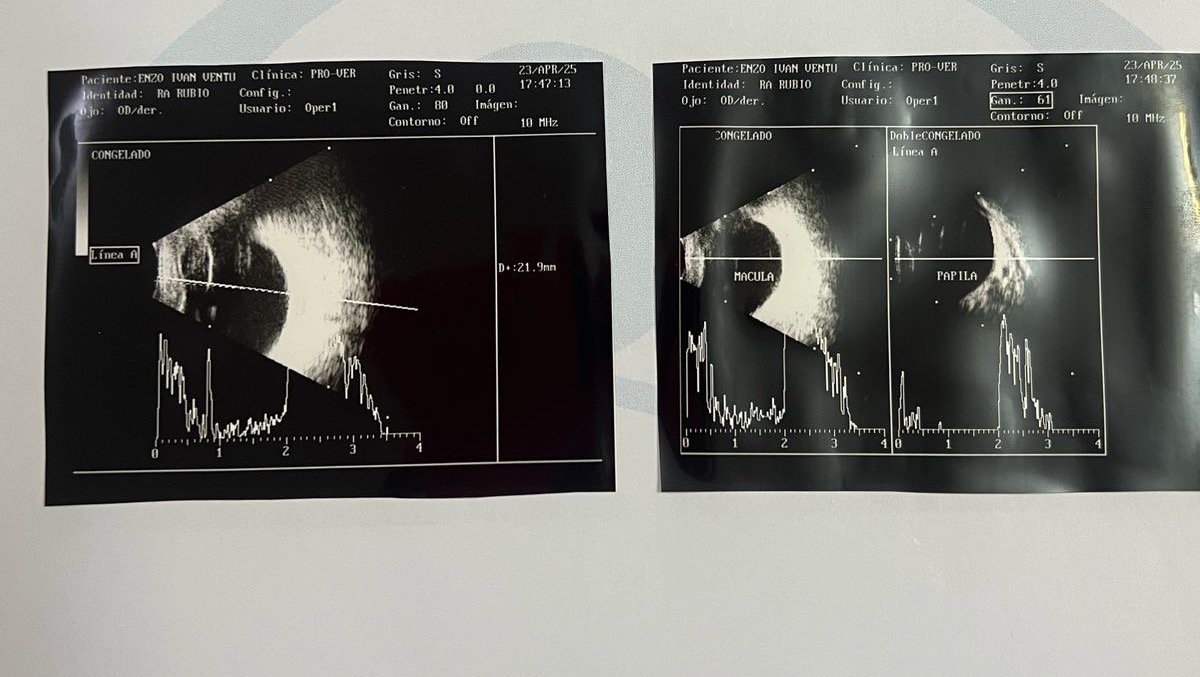

*Enzo’s Fight to See the World*

Enzo is our baby boy, just 1 year and 10 months old, and he has already gone through 7 major eye surgeries in his short life.

He was born with a rare condition called bilateral coloboma of the upper eyelids, which severely affects his ability to see and protect his eyes.

7. Emergency scleral graft surgery - Doctors discovered a damaged cornea and had to urgently place a scleral graft to protect the eye and prevent a possible retinal detachment.

What’s Next: A Keratoprosthesis (Artificial Cornea)

Enzo still cannot see, but there’s hope.

Due to the severity of his condition and the damage to his cornea, doctors have recommended a keratoprosthesis — an artificial cornea implant.

This is not a standard corneal transplant, but a much more complex and delicate procedure that is only performed in specialized medical centers.